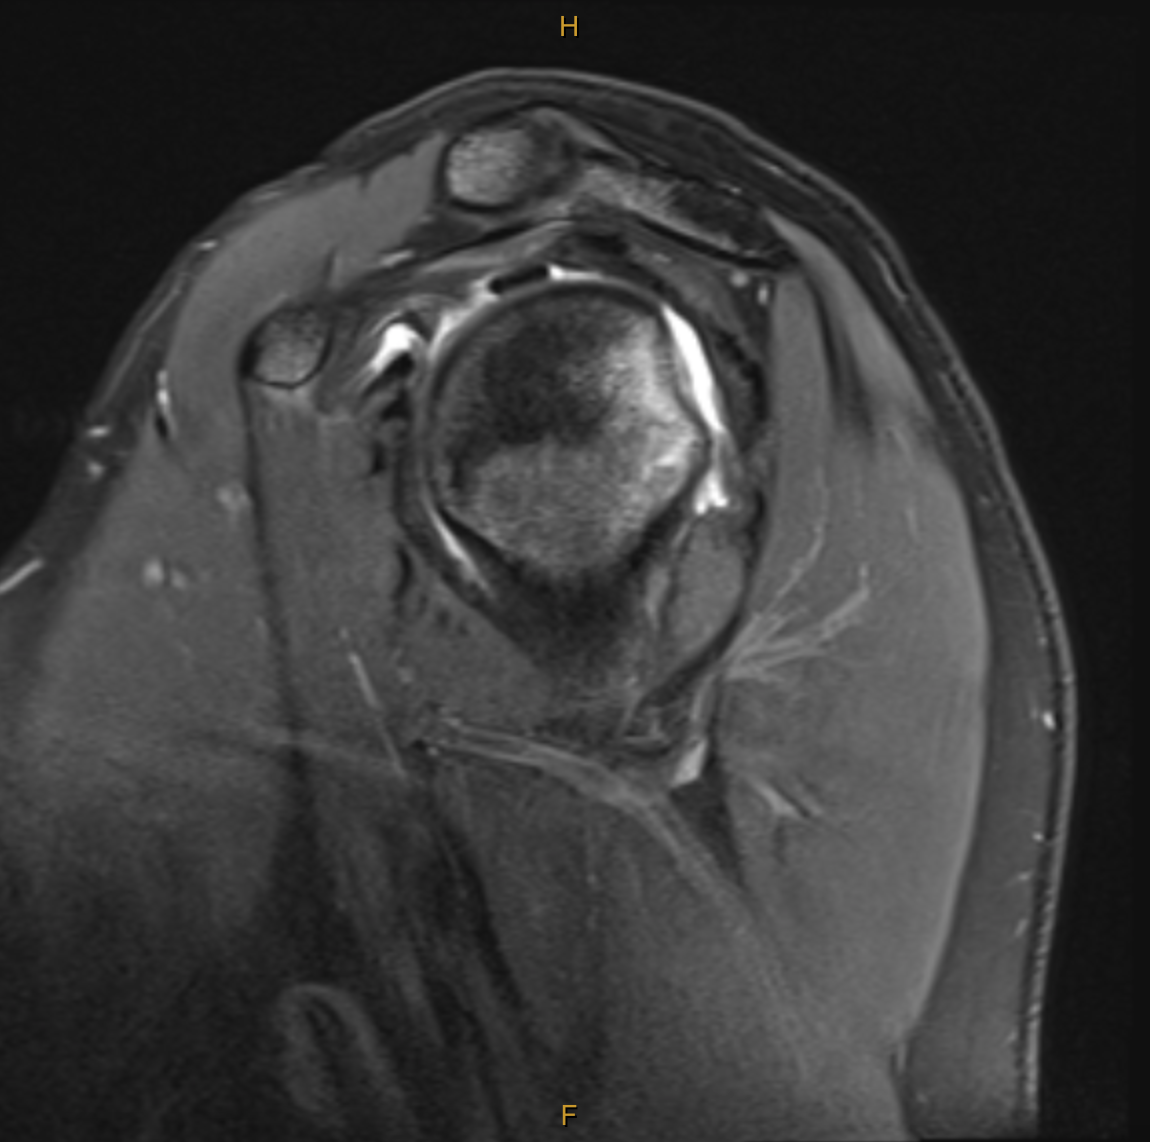

My clinical impression was the Ms C’s presentation was consistent with the event of an anterior dislocation and that MRI would best visualise the extent of tissue pathology. The report was incredibly detailed, and yet, there was additional structural damage which was not found until months later during surgery. The key findings (and my thoughts on their significance) are below:

Broad Hill-sachs lesion with underlying bone marrow oedema in keeping with recent anterior macroinstability event.

Impact fracture of the humeral head from contact on the glenoid. This fracture and indentation into the humeral head does not improve unless operated on and can lead to further instability and dislocation in positions of elevation and external rotation as the humeral head moves past the glenoid. This particular part of the injury is what is managed with the “remplissage” technique. (indication for surgery).

The bone marrow oedema can take between 3-6 months to settle (indication for wait and see).

Mild complex tear of the inferior to anterosuperior labrum extending from roughly the 6 o’clock position to the 10 o’clock position. [Fibrocartilaginous Bankart lesion]

No accompanying osseous Bankart lesion. [The glenoid was not fractured during dislocation]

There is slight elevation of the anterior glenolabral periosteum, consistent with some periosteal stripping.

No significant glenohumeral chondropathy.

Small joint effusion.

Intact cuff.

Not reported until surgery:Posterior labral tear and anteriorinferior chondral damage.

In addition to the exact MRI findings for this case, I have also added some images which outline the variants of a Bankart lesion and Hill-Sachs lesion below.